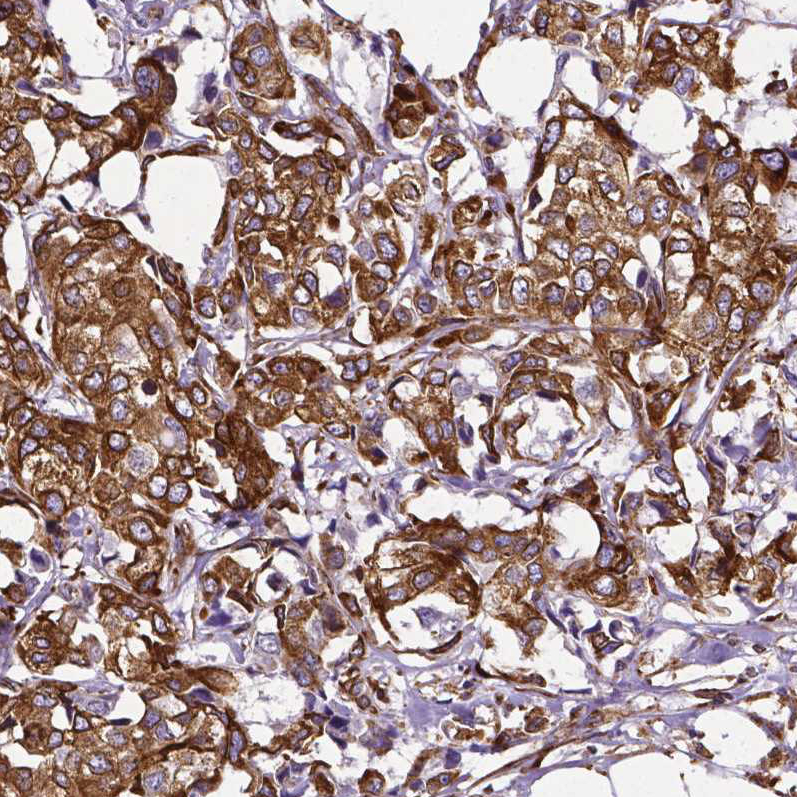

Immunohistochemical staining of human breast cancer shows strong cytoplasmic positivity in tumor cells.